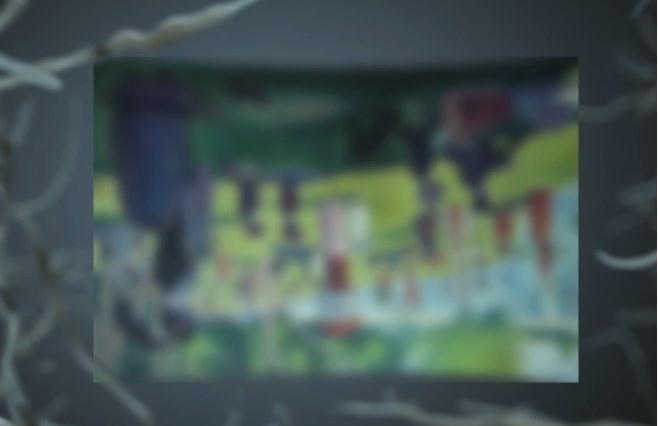

传统的白内障手术,在超声乳化的关键步骤制造切口和撕囊时,都是依靠医生手动操作。所以,医生的经验和技巧非常重要,切口会影响恢复速度和术后视力,容易产生机械变形和渗透,而手工撕囊的质量影响术后并发症和视觉质量。

随着技术发展,以飞秒激光辅助白内障手术技术为代表的,前沿手术方式正受到越来越多人的青睐。

飞秒激光可以代替医生的手工切口,预先分割囊膜内的混浊晶体,整个过程都有电脑扫描成像技术辅助,可以准确地制造切口并撕囊,使其光滑平整,还可以利用飞秒激光去除患者部分散光问题,再用超声波去除晶体。